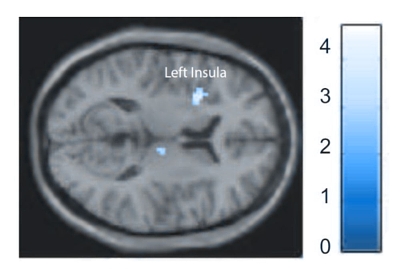

fMRI imaging study of the participants revealed that more activation of the left anterior insula was detected in the tVNS group compared to the sham treatment group. The insula is a key brain region that regulates emotions and saliency processing and has been implicated in the pathology of depression.

Caption: Activation map showing the brain region after tVNS stimulation. The region highlighted in yellow shows the left insula.

The results of fMRI were further corroborated by another earlier German study that confirmed an increased activation in the insula after tVNS stimulation. The researchers also found a simultaneous increase in MRI signal in the precentral gyrus (both sides), the right thalamus and the right anterior cingulate cortex. [2]